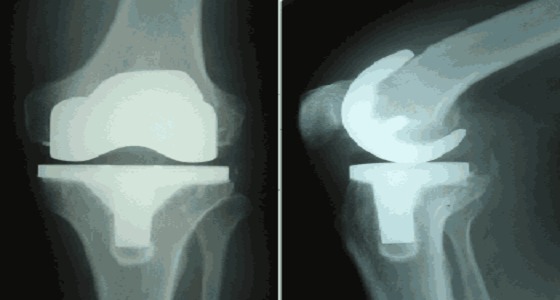

نجاح عملية تغيير ركبتي مريض بمكة